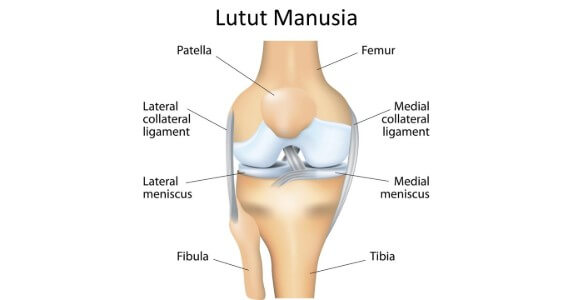

Nyeri Lutut - Gejala, penyebab dan menangani - Alodokter

Nyeri Lutut - Gejala, penyebab dan menangani - Alodokter